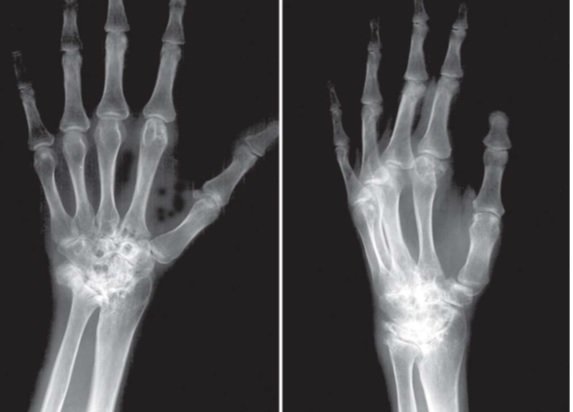

محققان کشور دستگاهی را برای درمان شکستگیهای مچ و ساعد دست ارائه دادند که علاوه بر آنکه زمان جراحی و پینگذاری را کمتر میکند، جراح امکان عکسبرداری همزمان با عمل جراحی از موضع آسیبدیده را دارد.

رویداد۲۴ با بیان اینکه این طرح با عنوان دستگاه "جا اندازی و فیکساسیون شکستگیهای ساعد و مچ دست" طراحی و ساخته شده است، گفت: در دنیا برای جا اندازی و فیکساسیون شکستگیهای ساعد و مچ دست ابزاری وجود ندارد. این در حالی است که جا اندازی و فیکساسیون شکستگیهای مچ دست و ساعد یکی از اساسیترین اقدامات در ارتوپدی به شمار میرود.

وی با بیان اینکه برای جا انداختن شکستگیهای ساعد و مچ دست از روش کشش استفاده میشده است، اظهار کرد: این روش در دنیا و ایران متداول است که برای درمان این نوع شکستگیها موضع تحت کشش دستی (Manual) جراح و یا متخصص ارتوپدی انجام میشود و از آنجایی که به صورت دستی انجام میشد، این اقدام همراه با خطا بوده است، به گونهای که به ویژه برای کشش مچ دست در بسیاری از مواقع فرد مصدوم دچار عوارض ناشی از این اقدام میشود.

به گفته وی، شکستگیهای ساعد و مچ دست به دلیل نبود امکاناتی نظیر " Fracture tableبرای شکستگیهای اندام فوقانی با مشکلات و پیچیدگیهایی روبرو است، از این رو اعمال جراحی شکستگیهای مچ دست و ساعد به یکی از جراحیهای پیچیده ارتوپدی تبدیل شده است و این دستگاه سعی دارد تا مانند fracture table بتواند به ثبات موضع جراحی در حین عمل و نیز جا اندازی بهتر شکستگیهای ساعد و مچ دست با مکانیسم منحصر بفرد خود که سبب حرکت ظریف استخوان و جا اندازی شکستگیها و در رفتگیها میشود، کمک کند.

قرهبگلو با بیان اینکه در این دستگاه با اعمال کششی که بر روی مچ و ساعد دست صورت میگیرد، شکستگیها جا انداخته میشود، گفت: علاوه بر آن، این دستگاه دقت بیشتری برای پینگذاری عضو شکسته دارد؛ چراکه بستر مستحکم برای اندام شکسته ایجاد میکند، از این رو عمل پینگذاری با دقت بیشتری نسبت به روشهای متداول خواهد بود و در نتیجه عوارض عمل کمتر خواهد شد.